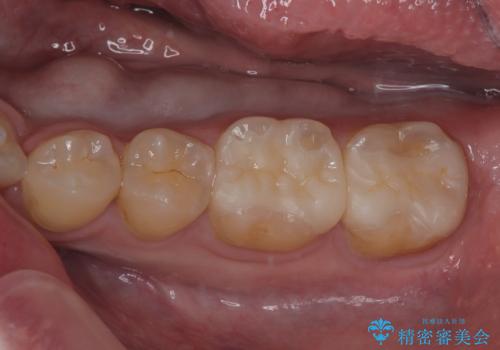

銀歯の下の虫歯を治したい オールセラミッククラウン・セラミックインレー修復